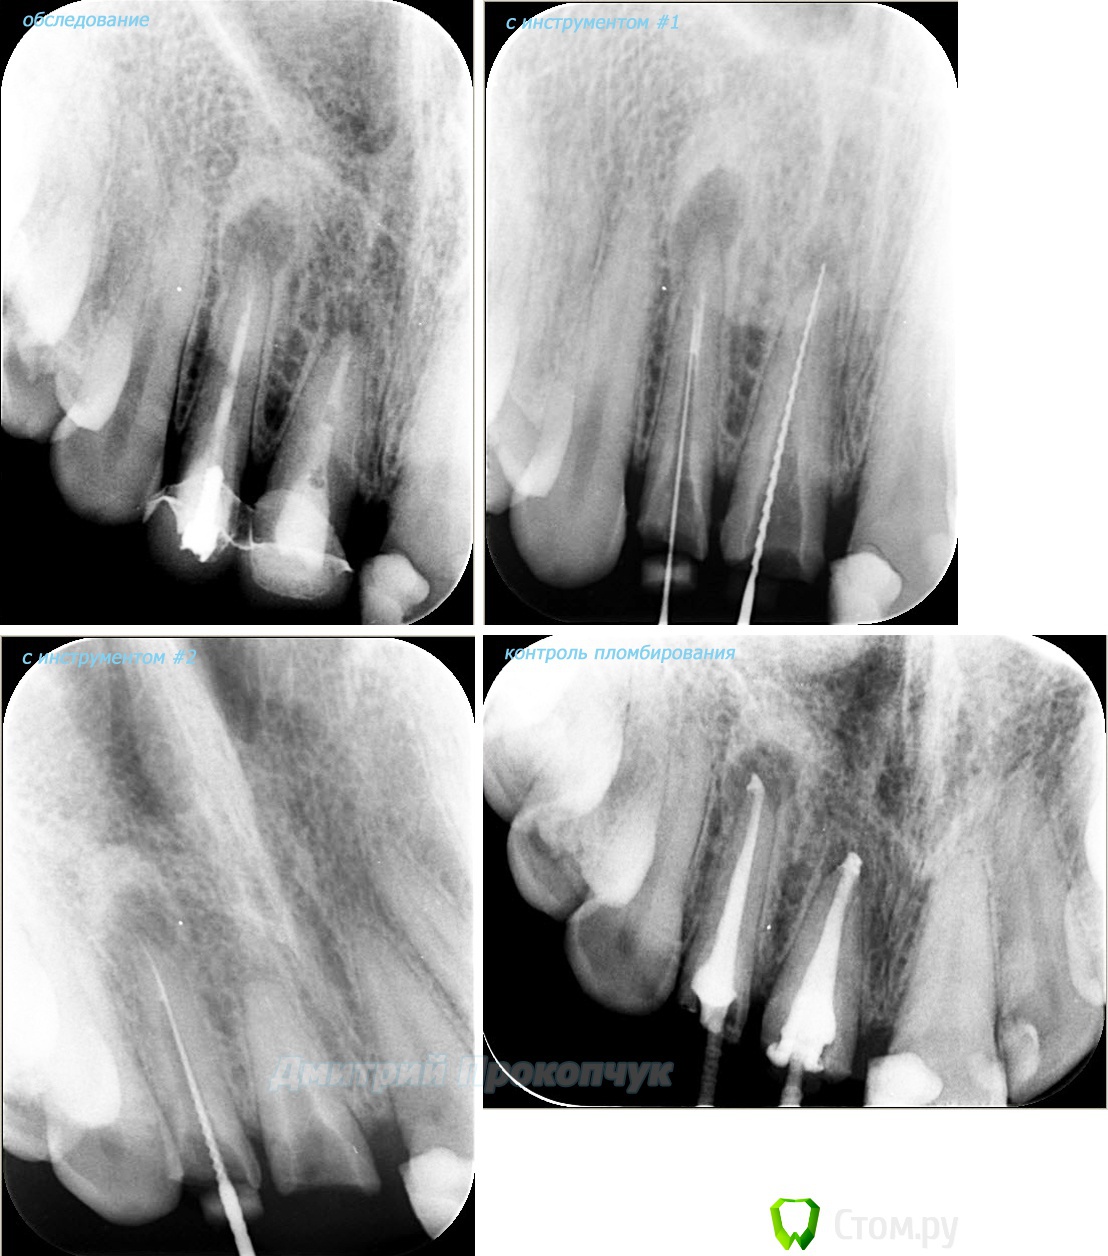

punkrat Опубликовано 16 сентября, 2014 Поделиться Опубликовано 16 сентября, 2014 Коллеги, тема , возможно, не имеет смысла просто приятная мне эндодонтия, сохранил с предыдущего места работы. Да, будь я проклят, я все знаю, НИГДЕ НЕТ КОФЕРА, на новом месте с этим норм. В общем если посчитаете, что я недостоин постить тут свои снимки, то так тому и быть, удалю тему.. 01. плановый ретрит 46ого и результат через 7 месяцев. Осложняющим моментом тут было то, что длина каналов была около 26 мм... 02. первичное эндо 34 (подготовка к ортопедии) + бонус - ретрит 35 03. ретрит 26 (подготовка к ортопедии) 04. ретрит 15, 16 (подготовка к ортопедии). основная сложность была в ретрите 15 - он был запломбирован термафилами, да еще снабжен свш... 05. ретрит 27 (подготовка к ортопедии). Ничего особенного, со временем посмотрим какова будет убыль этого совсем немаленького разрежения 06. ретрит 13. Разумеется пришлось выбивать вкладку, а потом еще попилить 3-4 миллиметра цемента, но, таки попилил куда нужно... 07. ретрит 17 (подготовка к ортопедии). В данном случае я, кажется, потратил больше времени на снятие литого моста, чем на лечение 17)) 08. ретрит 16 (подготовка к ортопедии). Снимка с инструментом нету, поскольку, визиограф сломался и его делал на пленку. 15 разумеется тоже перелечен... 09. плановый ретрит 16 10. первичное эндо 36, рядовой случай что дистальный щечный удалось найти не сразу, он был спрятан под нависающим дентиклем 11. ретрит 12, 11 (подготовка к ортопедии). Казалось бы, рядовой случай, если бы корневые каналы обоих зубов не были бы налухо забиты резорцин-формалиновой смесью... 12. ребенок 9ти лет, острый пульпит 46, попробовал оставить витальным. Пока полет нормальный, но даже если придется делать эндо в последствии, лучше когда оно будет сделано в более старшем возрасте... 13 Ссылка на комментарий

punkrat Опубликовано 17 сентября, 2014 Автор Поделиться Опубликовано 17 сентября, 2014 (изменено) Какой силер использовали? ну чтобы сразу обо всем, а не только о силере. Механика: протейперы + профайлы + уз + ручные файлы (сталь до 15, с 15 - NiTiфлексы), пломбировка: термофил + АН+ Изменено 17 сентября, 2014 пользователем punkrat Ссылка на комментарий